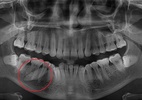

Um cálculo gigante foi encontrado na glândula salivar de um homem de 37 anos, na Índia. Por ser muito raro pedras com 1,5 cm ou mais neste local do corpo, o caso foi reportado no periódico BMJ Case Reports, no dia 28 de fevereiro.